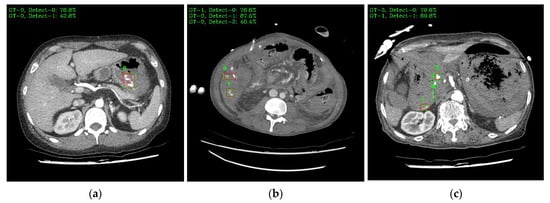

Figure 9 shows a visual representation of the results of lesion detection using the AH detector. Each image used for detection contains at least one GT-Box (green rectangle), which is the correct region. A P-Box (red rectangle), which is the detected region, is displayed according to the number of lesions detected and is not displayed when detection fails. The green text in the upper left corner of each image shows the index number of the GT-Box, index number of the detected P-box, and information about the IoU score. For example, Figure 9a shows that, for one GT-Box with a GT-Box index number of 0 (GT-0), two P-Box index numbers (Detect–{0, 1}) were generated with IoU scores of 76.8% and 42.8%. In addition, as shown in Figure 9c, out of the four GT-boxes with GT box index numbers GT–{0, 1, 2, 3}, only GT–{1, 3} was successfully detected, resulting in P-boxes with IoU scores of 69.8% and 79.6%, respectively.

Figure 9. Example images of the AH-lesion detected using the AH detector. Green boxes indicate GT-Box, and red boxes indicate P-Box. Green text is GT-Box index, P-Box index, and IoU score: (a) single GT-Box and detected two P-Box; (b) two GT-Box and detected each single and two P-Box; (c) four GT-Box: detected two P-Box and missed two P-Box; (d) single GT-Box: detected single P-Box; (e) two GT-Box: detected two P-Box; (f) three GT-Box: detected three P-Box.